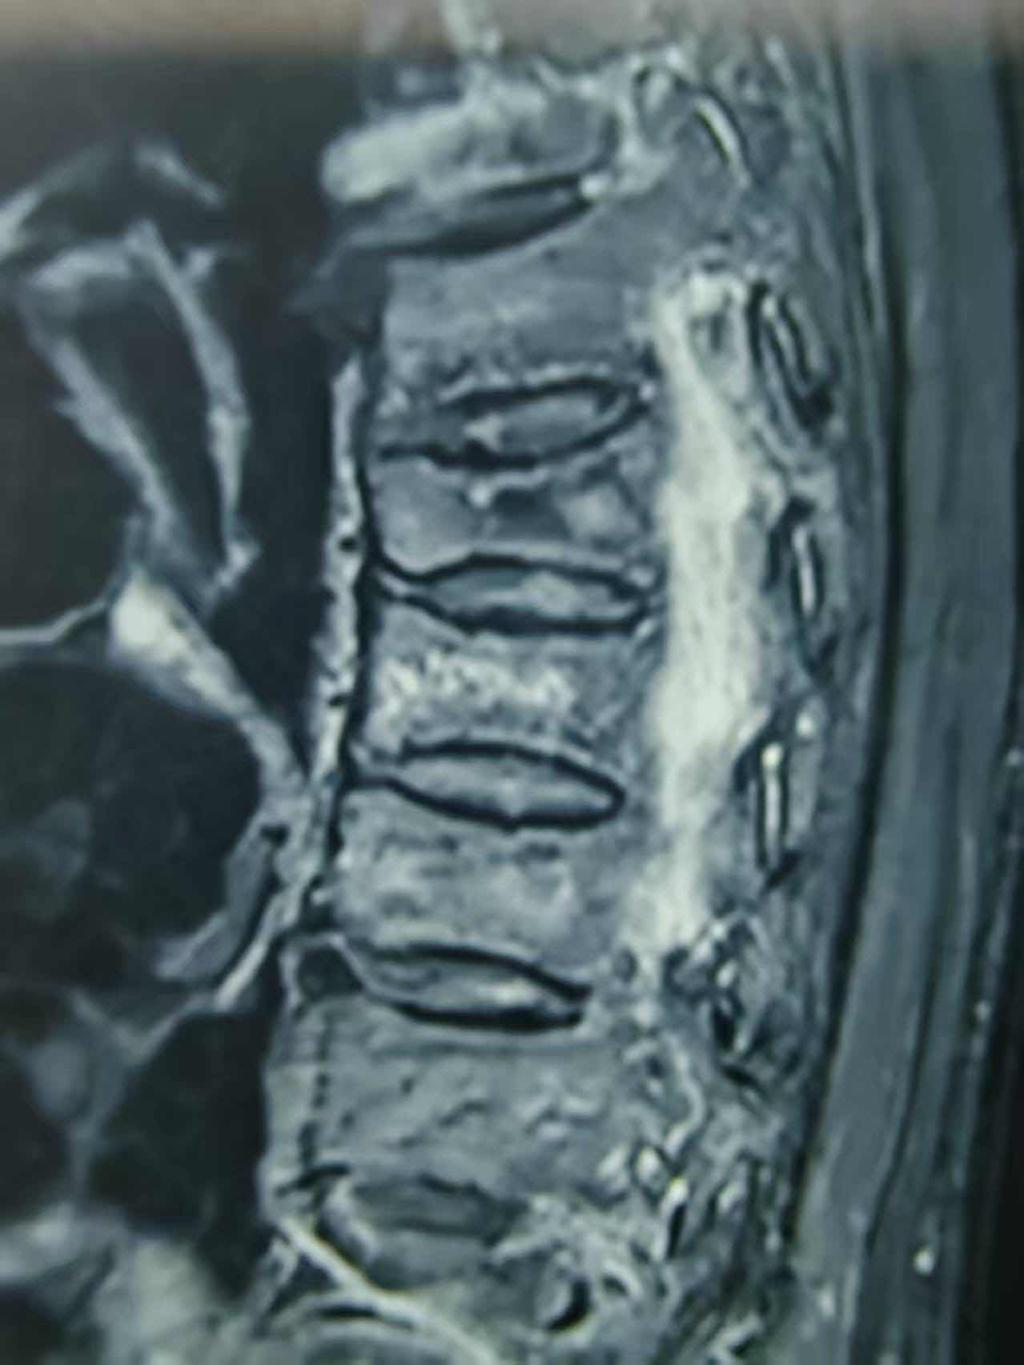

老人起床翻身后出现背部及胸部疼痛,刚开始以为只是个简单的扭伤,但是疼痛却越来越重,辗转多家医院,最后才确诊是胸7胸8椎体骨折。因为老人年龄太大,均建议采取保守治疗。

我们的骨科二病区团队没有因为患者高龄而退缩,张宏主任联络麻醉科手术室和胸外科,通过严谨评估,为其“量体裁衣”,实施了精准、微创的“骨科机器人辅助下胸椎椎体成形术”治疗。